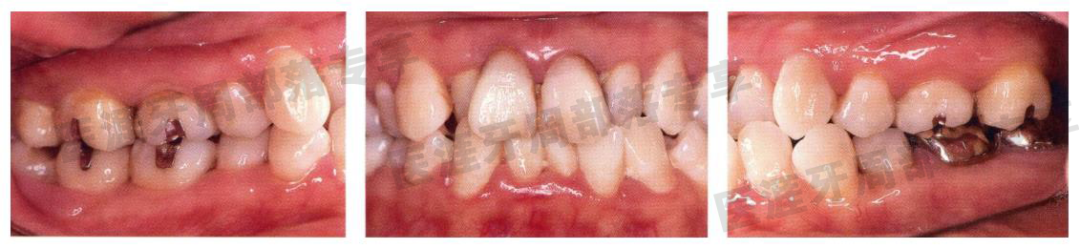

怎么选洁牙器械5个要点带你学习器械洁牙_https://www.jmylbn.com_新闻资讯_第39张

护理时的口内照(2007 年4 月)

虽然有牙菌斑,但牙龈情况比起初诊时改善很多。不过右上 7 中途在其它医院被拔去。

怎么选洁牙器械5个要点带你学习器械洁牙_https://www.jmylbn.com_新闻资讯_第40张

护理时的X 光片(2006 年4 月)

距离初诊 9 年,牙槽嵴线稳定,预后良好。

左上 7、左下 6 的根分叉病变时刻留意并进行了清创。研究是否进行截根术。